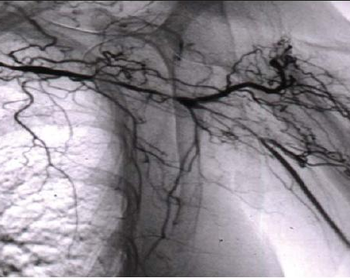

Whatever is causing this woman’s hip pain, her x-ray film looks quite severe. The diagnosis was correct 40 years ago, but it couldn’t be treated effectively then. What’s the problem?